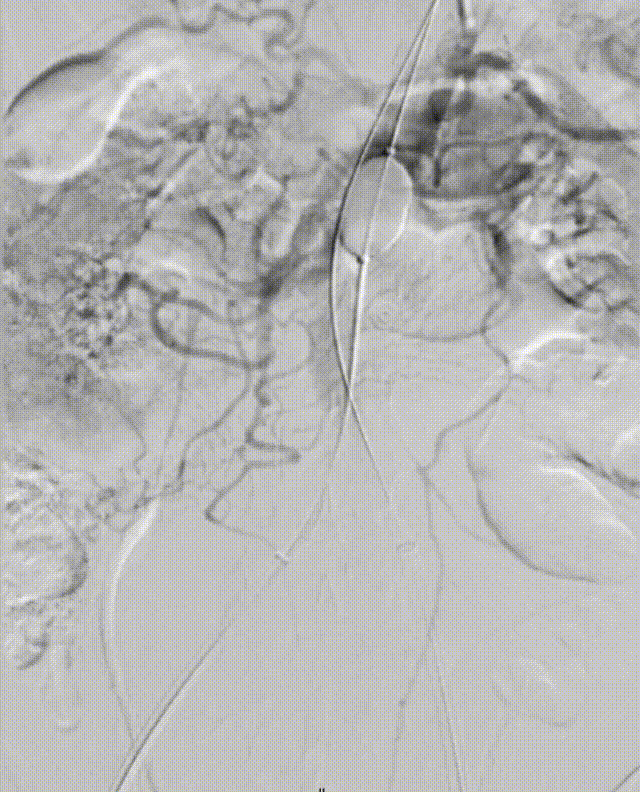

5. 经右侧股总送入泥鳅,再通过泥鳅输送另一个MOB球囊在原球囊远端,尝试将近端的球囊回收,同时展开远端球囊,在远端球囊被造影剂完全展开贴合血管壁以前,将原MOB球囊撤出。

6.将右侧球囊往上输送至高于肾动脉的位置以留出空间进行支架输送等步骤,因血流湍急,球囊未能实现在理想位置的展开以进行近端血流阻断

7. 重新送入左侧球囊至右侧球囊远端,对右侧球囊内造影剂进行小部分回抽,使左侧球囊通过球囊与血管壁的间隙继续往近端输送,充盈左侧球囊使其部分展开,捏住左侧球囊输送杆,维持左侧球囊位置,降低右侧球囊受到的血流压力。

8. 将右侧球囊继续往近端推动,超过肾动脉以及经左锁骨下动脉预置的造影椎管,充分使球囊充盈阻断血流,此时能实现右侧球囊在高于肾动脉的理想位置固定。

gore医疗怎么样「漫腹精论」髂合时宜 精益求精——双MOB球囊导管辅助腹主动脉覆膜支架急诊治疗破裂巨大髂动脉瘤_https://www.jmylbn.com_新闻资讯_第18张